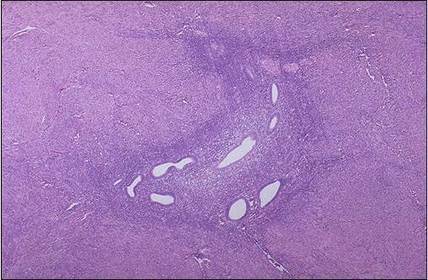

Diagnóstico e micro. Hiperplasia Endometrial Complexa de Baixo Grau. Glândulas proliferadas, tortuosas, irregulares e justapostas sem atipias.